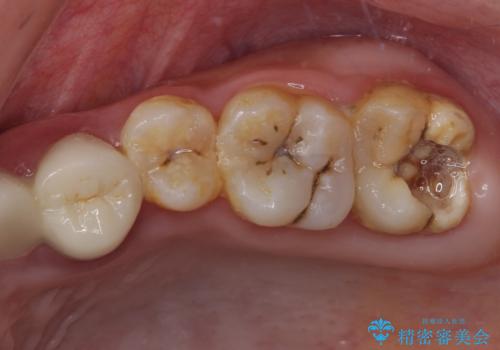

[ インプラント治療 ]失った奥歯を回復したい

![[ インプラント治療 ]失った奥歯を回復したいの症例 治療前](https://seimitsushinbi.jp/wp/wp-content/uploads/2021/11/036b501e44e72b51304eaa0dd62d1613-500x350.jpg?v=1637928855)